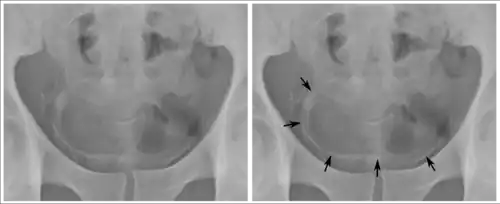

Os ovos podem ficar alojados no fígado,[25] levando a hipertensão portal, esplenomegalia, acúmulo de líquido no abdômen e risco de vida potencial dilatações ou áreas inchadas no esôfago ou trato gastrointestinal que podem rasgar e sangrar profusamente (varizes esofágicas). Esta condição pode ser dividida em duas fases distintas: esquistossomose hepática inflamatória (reação inflamatória precoce) e esquistossomose hepática crônica. As espécies mais comuns que causam esta condição são S. mansoni, S. japonicum, e S. mekongi.

A ultrassonografia em mãos experientes pode fazer o diagnóstico, sendo patognomônico a fibrose e espessamento periportal, hipertrofia do lobo hepático esquerdo e aumento do calibre da mesentérica superior.[41]